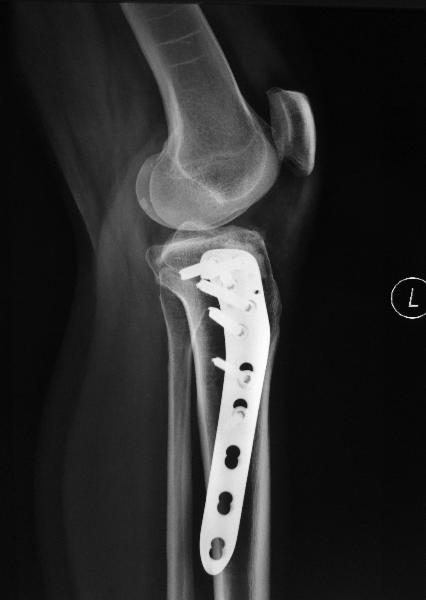

The fracture was openly reduced and stabilized using special locking plates.

The x-rays taken at 6th week after the surgery showed good fracture reduction and healing.